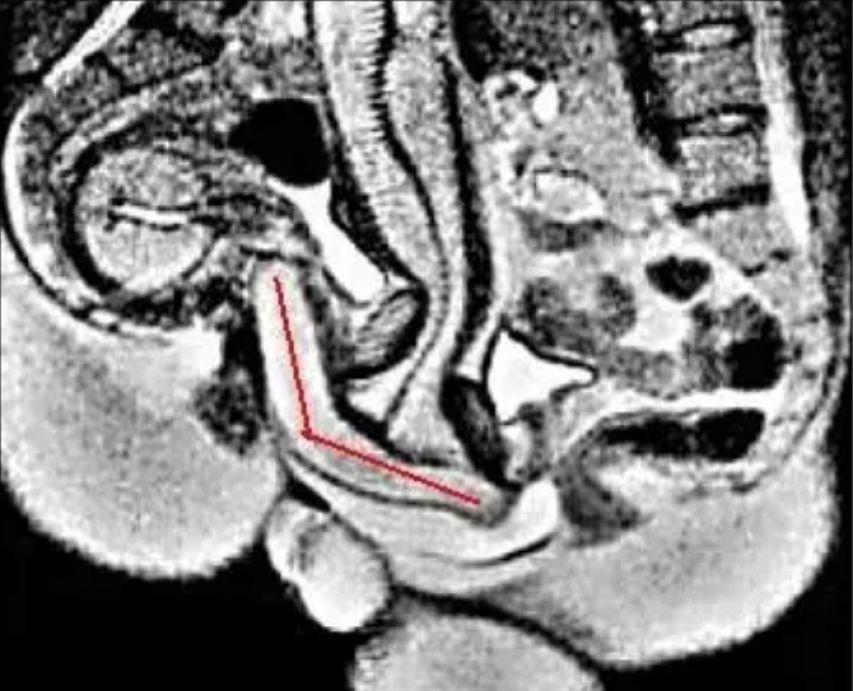

用核磁成像拍攝性行爲過程

威利布羅德·魏吉瑪·舒爾茨(Willibrord Weijmar,爲方便閱讀,後面簡稱“舒爾茨”)一直很好奇,人類在進行性行爲時,身體到底有什麼變化?當雙方達到愉悅值最高點時,身體又會產生怎樣的奇妙反應?

舒爾茨和他的團隊通過當地的媒體招募到了8對志願者夫妻,請他們在覈磁成像設備中進行性行爲,再通過核磁成像觀察志願者在整個過程中的生理反應,包括雙方私密處細微變化。

結果還真讓舒爾茨團隊觀察到了詳細變化:

在親密行爲尤其是達到興奮狀態時,人體會心率加快、呼吸頻率加快、血壓上升,同時耗氧量極速增加(還是個有氧運動),女性的子宮沒有太大的變化,而男性的生殖器會在過程中呈現120°的迴旋鏢形狀。

【核磁成像結果】

志願者在整個過程中做出了相當大的貢獻,因爲在拍攝前,男性被要求喫藥,在過程中,舒爾茨和團隊工作人員也會隨時叫停,以便極其拍攝出更清晰的照片。

1999年,舒爾茨將相關的研究結論發表在醫學頂刊《英國醫學雜誌》上,又在2000年獲得了搞笑諾貝爾獎,但他對性的研究以及使用核磁成像研究的方法,都帶給了人類許多思考。